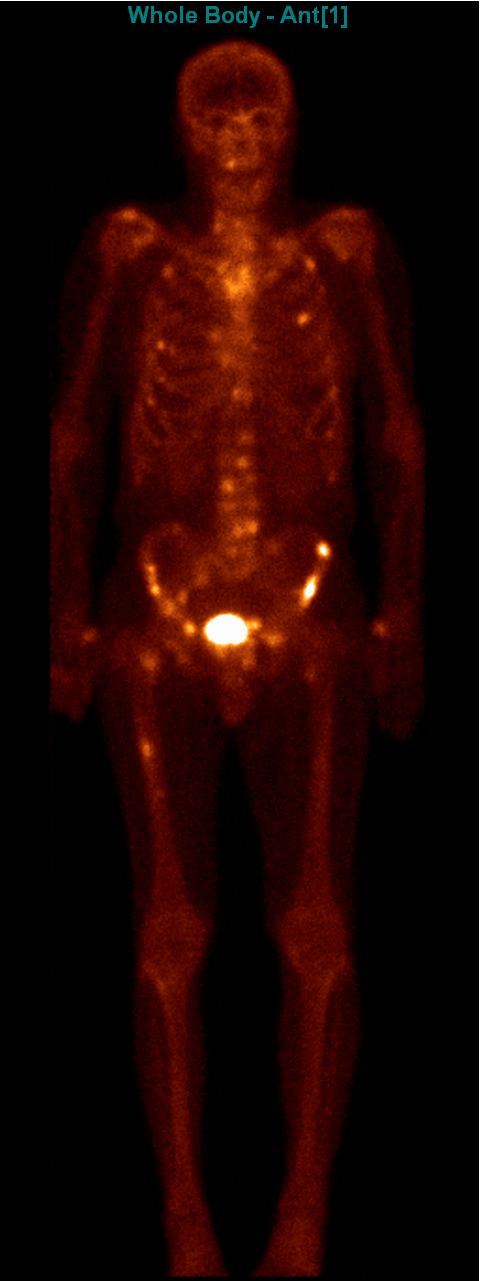

Test iframe

2. FDG PET Maximum Intensity Projection (MIP) image. There is a large biological contrast between the normal and the pathologic tissues. Right sided breast cancer, ipsilateral metastatic lymph nodes and multiplex metastases in the lung. Physiologically elevated FDG uptake is seen in the brain, salivary glands, tonsils, liver and the spleen as well as in the bone marrow and at certain segments of the intestines. Also, there is increased FDG activity in the kidneys and the urinary bladder due to excretion.